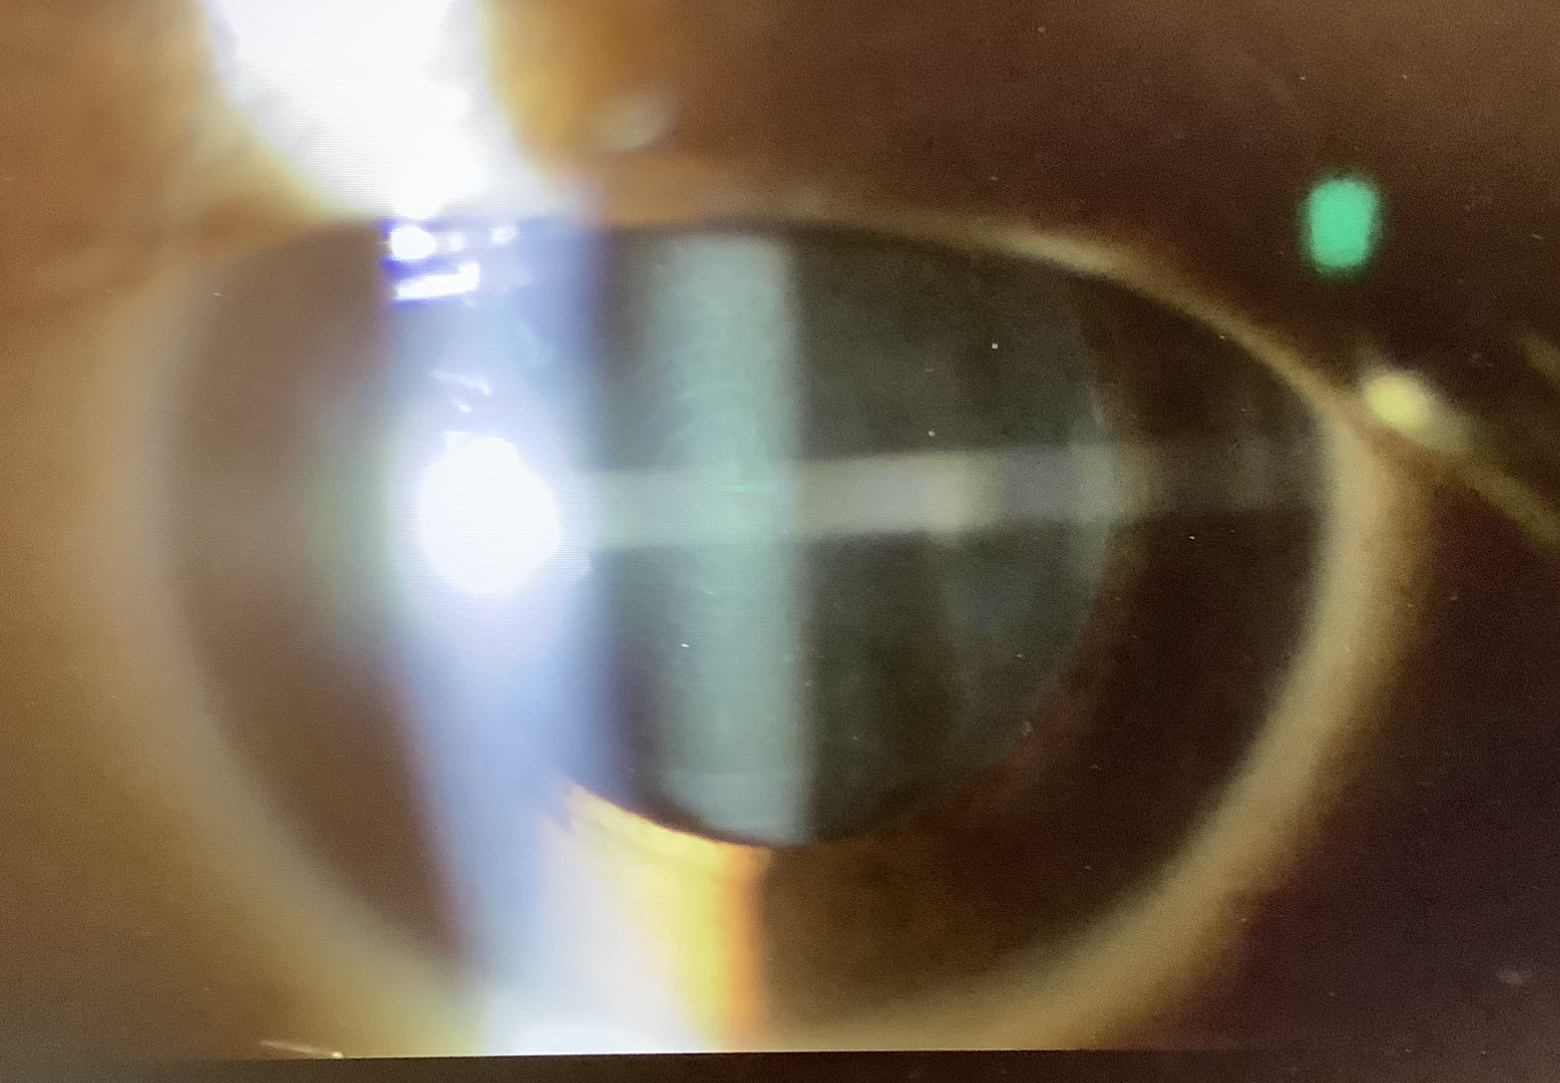

今日、眼内レンズの入れ換えのご相談でいらっしゃった40代半ばの女性の方は、他院で左眼を昨年の4月に、右眼を11月に多焦点レンズを使った白内障の手術(右眼はファインビジョン 左眼はパンオプティクス)を受け、右眼の見え方がかすんでおかしいということで受診されました。右眼の視力は遠方1.2 中間1.0 近方0.8と十分良好で、左眼よりもよいくらいで、レンズもきれいに入っており、所見上は術後の経過としては、全く問題ないと思いました。ただ、視力自体は良好なものの、左眼に比べると、レンズの入っている袋(後嚢)の混濁がやや目立ち、後発白内障が影響しているように思われました。後発白内障自体は、YAGレーザーで簡単に治療(後嚢切開)できるので、心配ないのですが、後嚢切開をしてしまうと、レンズの交換が難しくなってしまうので、レンズの入れ換えの可能性があるならば、もう少し後嚢を温存し、経過をみながら、やっぱり後発白内障が見えにくさの原因であれば、徐々に今より見えにくくなってくるので、そうなれば、より判断しやすく、後発白内障の治療をしたらよいのではとお話しさせていただきました。